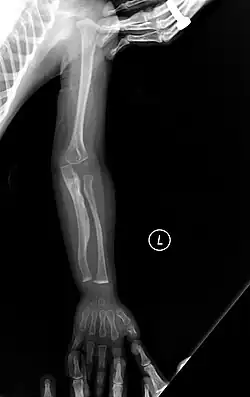

The main symptom of osteogenesis imperfecta is fragile, low mineral density bones; all types of OI have some bone involvement.[5] In moderate and especially severe OI, the long bones may be bowed, sometimes extremely so.[28] The weakness of the bones causes them to fracture easily—a study at the Endocrine Unit at the National Institute of Child Health in Karachi, Pakistan found an average of 5.8 fractures per year in untreated children.[29] Fractures typically occur much less after puberty, but begin to increase again in women after menopause and in men between the ages of 60 and 80.[1]: 486

Diagnosis is typically based on medical imaging, including plain X-rays, and symptoms. In severe OI, signs on medical imaging include abnormalities in all extremities and the spine.[97] As X-rays are often insensitive to the comparatively smaller bone density loss associated with type I OI, DEXA scans may be needed.[5]: 1514

An OI diagnosis can be confirmed through DNA or collagen protein analysis, but in many cases, the occurrence of bone fractures with little trauma and the presence of other clinical features such as blue sclerae are sufficient for a diagnosis. A skin biopsy can be performed to determine the structure and quantity of type I collagen. While DNA testing can confirm the diagnosis, it cannot absolutely exclude it because not all mutations causing OI are yet known and/or tested for.[83]: 491–492 OI type II is often diagnosed by ultrasound during pregnancy, where already multiple fractures and other characteristic features may be visible. Relative to control, OI cortical bone shows increased porosity, canal diameter, and connectivity in micro-computed tomography.[98] OI can also be detected before birth by using an in vitro genetic testing technique such as amniocentresis.[99]

Acute bone fracture care

Bone fractures are treated in individuals with osteogenesis imperfecta in much the same way as they are treated in the general population-OI bone heals at the same rate as non-OI bone.[1]: 431 A greater emphasis is placed on using lightweight materials to immobilize the fracture, as in moderate or severe types of OI, using heavy casts, such as hip spica casts, can cause fractures at the bones at the boundaries of the cast, as well as generalized osteopenia.[1]: 431 The lightweight cast or splint is then replaced with a removable orthosis after a few weeks and once evidence of union is seen on X-ray.[1]: 431 To prevent a nonunion or malunion, all fractures should be immobilized, even if the fracture seems trivial (microfracture),[1]: 439 as people with OI are at greater risk of nonunion.[1]: 438